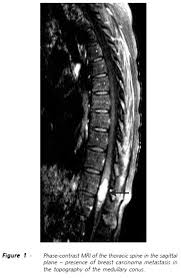

Metastatic Spine Tumors

Metastatic Spine Tumors from embed.widencdn.net